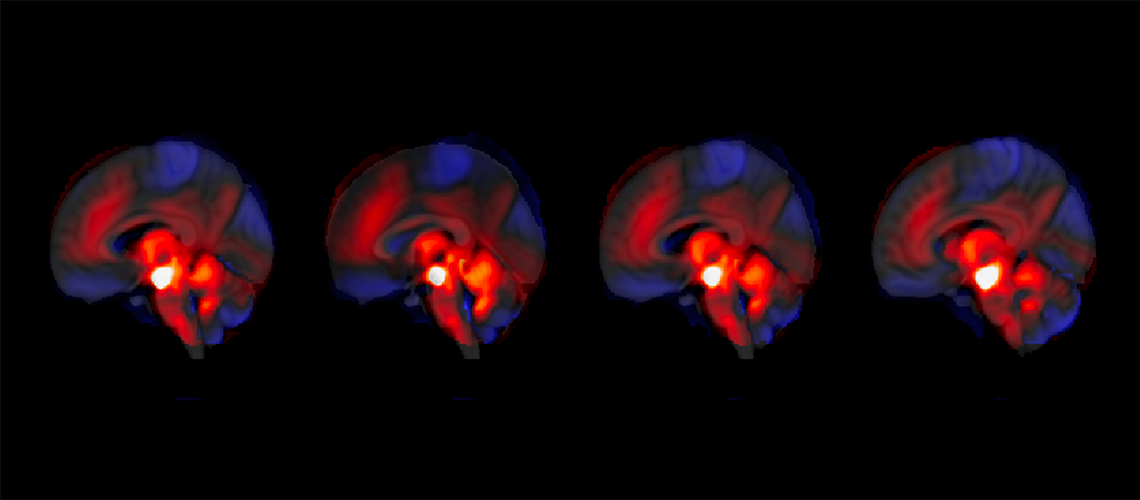

Imagem de ilustração da conectividade entre o cerebelo e a ATV.

© Thomas Bolton